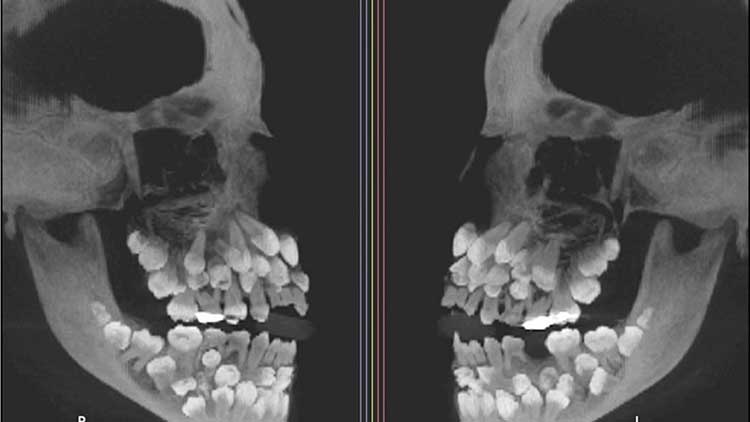

현지시간 17일 VN익스프레스 등에 따르면 위쪽 유치 1개를 뽑기 위해 병원을 찾은 브라질에 사는 11세 소녀가 엑스레이 촬영을 통해 유치 18개와 영구치 32개 등 총 81개를 발견했다.

해당 질환은 ‘다발성 과잉치증’으로 성인 기준 32개인 정상 치아 수를 넘는 추가 치아가 다수 존재하는 선천성 이상을 말한다고 외신은 전했다.

과잉치는 보통 1개에서 2개 정도만 나타난다.

연구팀은 정밀 영상 검사를 통해 치아의 정확한 위치를 파악했다.